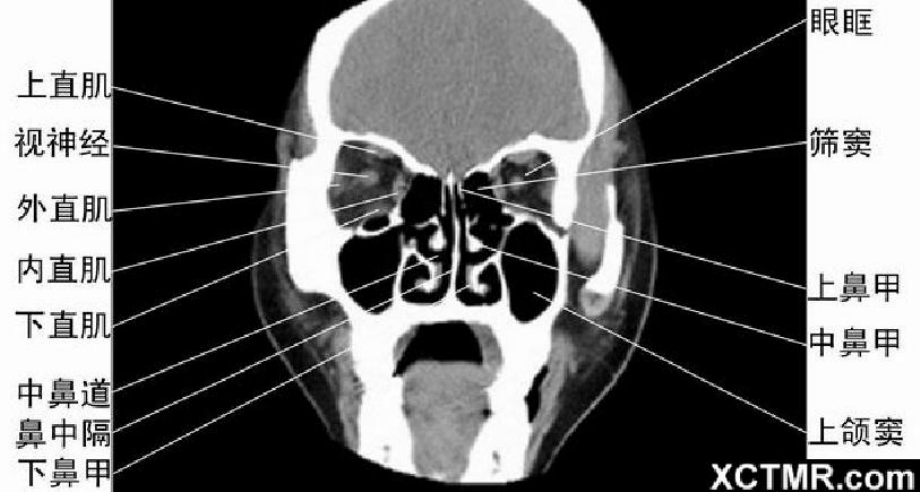

头颈五官CTppt课件